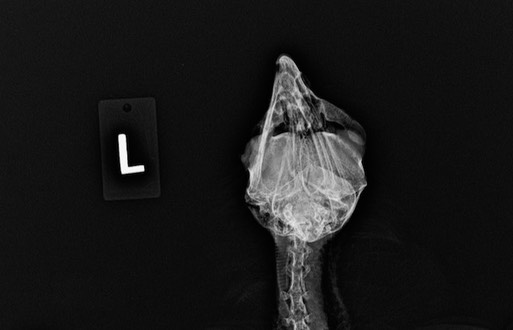

Red-tailed Hawk 22-080

A Red-tailed Hawk found in Yakima had damage to his left eye and skull from a gunshot injury. The injuries were not repairable and he was euthanized.

Common Raven 22-081

A Common Raven in Hermiston had a badly damaged left eye. Necropsy determined he had been shot. A projectile had entered on the right side of the skull and exited on the left side.

Bald Eagle 22-083

An immature Bald Eagle was found near Enterprise, OR. A radiograph showed the eagle had been shot. The damage was not repairable and the eagle was euthanized.